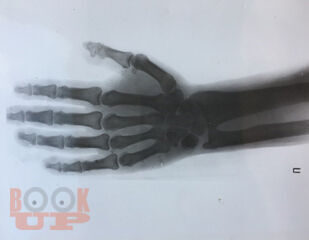

В пособии представлены редкие, сложные в плане диагностики и лечения случаи из практики, необычные дебюты известных заболеваний, паранеопластические синдромы, комплексы органной патологии, вызванные лекарственными препаратами; описан ранее не известный вариант разрыва эндокарда с образованием расслаивающей субэндокардиальной аневризмы левого желудочка при коронарной болезни. Собранные воедино клинические случаи подводят итог творческой работы большой группы клиницистов многопрофильного лечебного учреждения клиники госпитальной терапии Ставропольского медицинского университета. Обсуждаемые вопросы представляют интерес для специалистов разных областей медицины, в первую очередь, терапевтов, а также студентов старших курсов медицинских вузов, имеющих интерес к клинической работе.